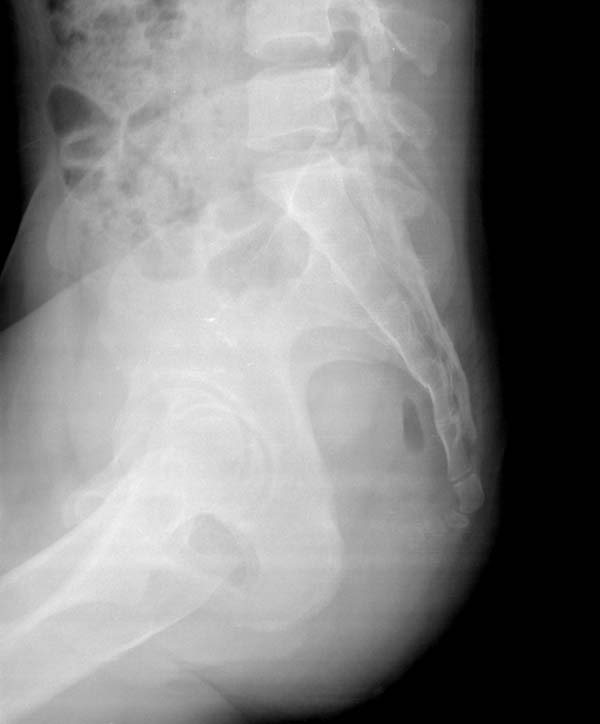

女 23  外伤来诊

看不太清,好像有骨折

未见骨折.

大家在结合侧位片看看

骶1椎体隐形脊柱裂,尾骨脱位成角畸形,骶尾部未见明显骨折征象。

第四骶骨前面皮质断裂【平片】骨折

骶4椎体骨折

考虑骶4椎体骨折

可能是个骶前孔的部分容积效应吧,看上去不太像骨折

考虑骶4椎体右侧骨折。